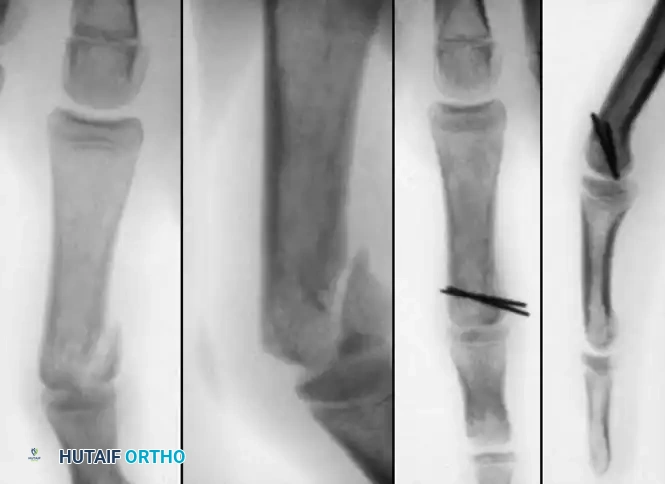

Diaphyseal fractures of the phalanges are common and usually amenable to closed reduction and splinting (e.g., buddy taping or an intrinsic-plus splint). However, in older children or in cases of severe instability, reduction cannot be maintained, necessitating internal fixation.

Image

Percutaneous Pinning Technique:

1. The short distal fracture fragment is clinically aligned with the middle phalanx by gentle hyperextension of the proximal interphalangeal (PIP) joint.

2. A K-wire is aligned clinically with the middle phalanx on the lateral side and drilled into the distal fragment.

3. A second K-wire is inserted on the contralateral side at a 45-degree angle to the proximal phalanx.

4. With both K-wires secured in the distal fragment, the fracture is reduced by bringing the PIP joint into slight flexion.

5. The wires are then advanced across the fracture site to emerge at the mid-diaphysis of the proximal segment, ensuring rigid, crossed-wire stability.